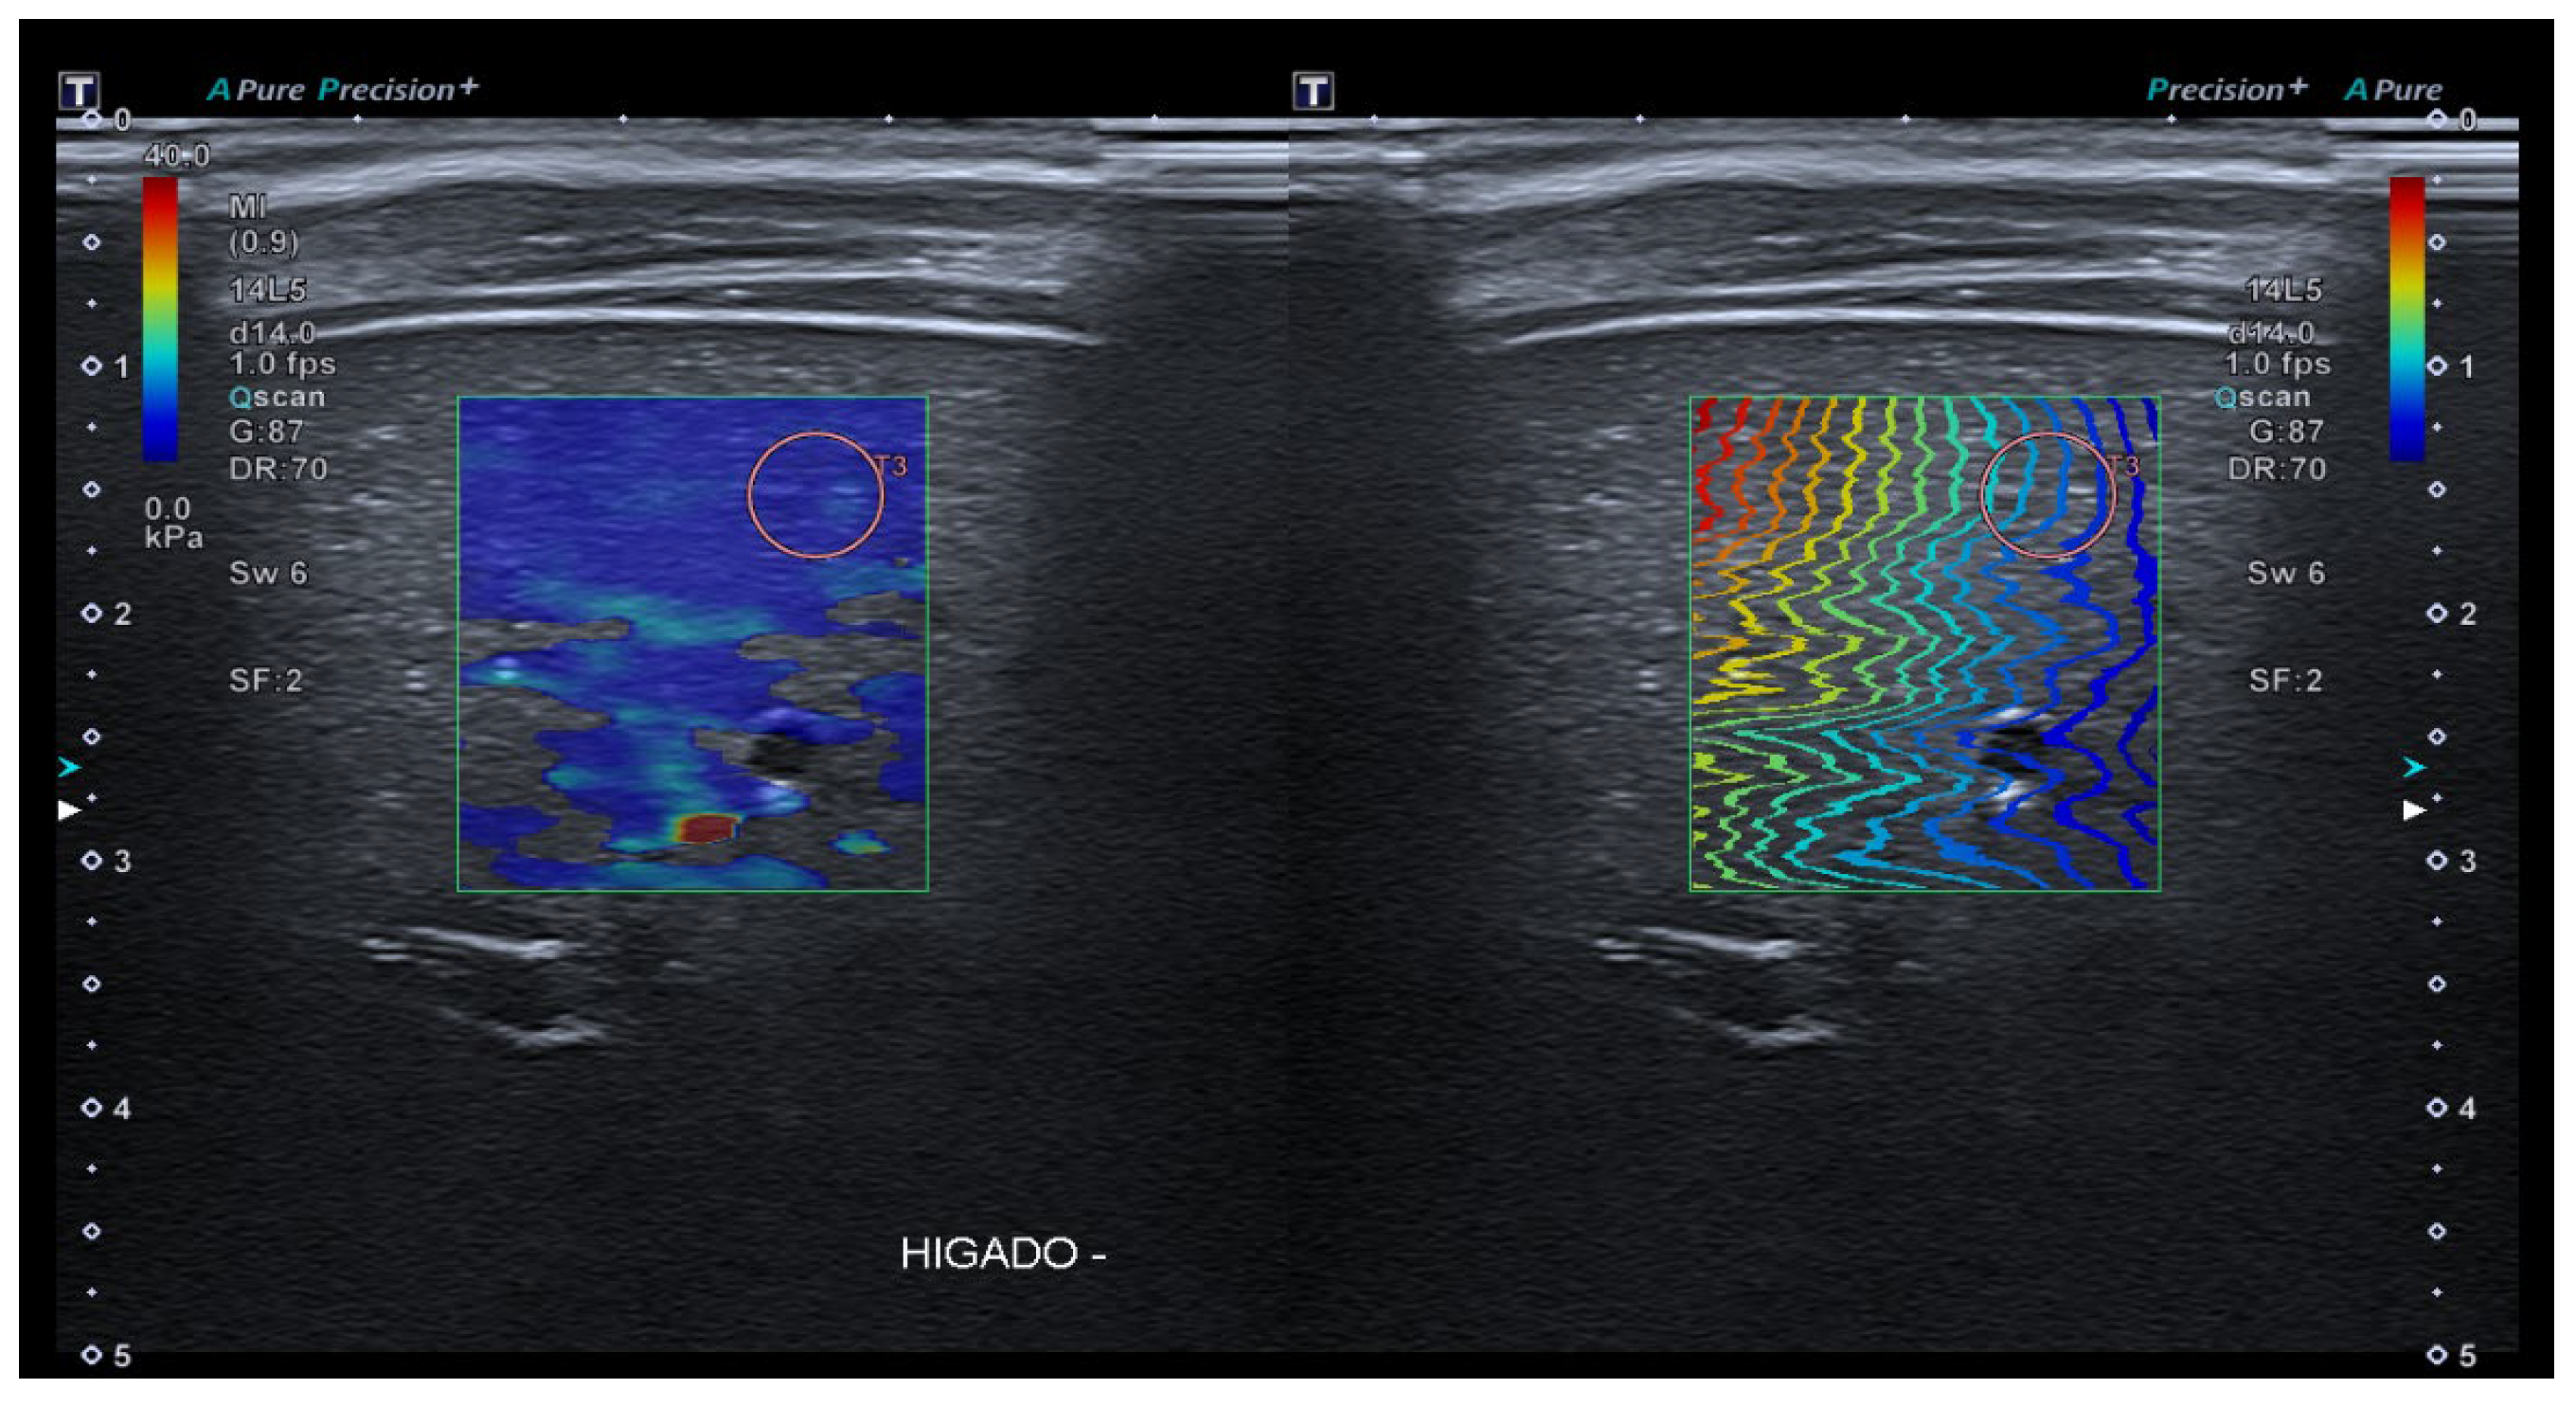

- 2D-Shear Wave Elastography (SWE): This is the latest and newest shear wave imaging technique. Like ARFI or pSWE, it uses acoustic radiation stimulation but, in this case, it rapidly scans multiple focal areas. This creates a virtual cylindrical shear wave cone that allows for the real-time monitoring of shear waves in 2D to measure their velocity, which is displayed on a quantitative colour map superimposed on a B-mode image (Figure 5). SWE has been extensively applied to characterize liver fibrosis [30,31], breast masses [32,33], prostate cancer lesions [34], thyroid nodules [35] and cervical lymph nodes [36]. In these contexts, SWE displayed low variability with respect to SE [37].